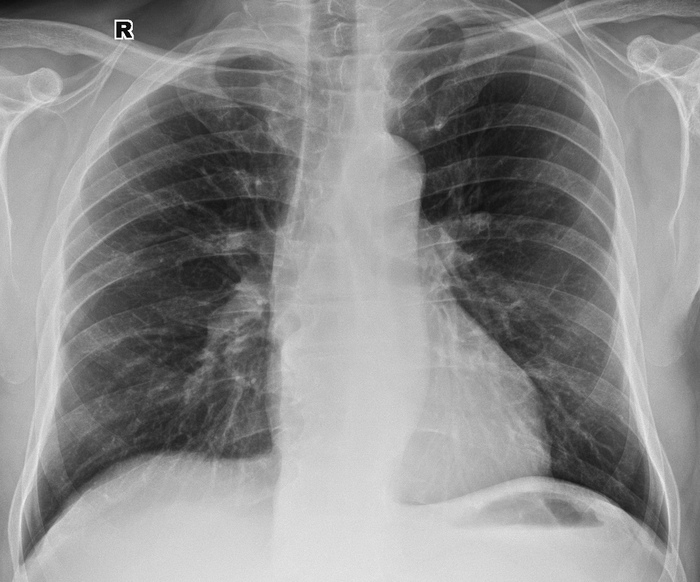

История 5. Метастазы рака нисходящей кишки в легкие

Интересная, но очень грустная серия снимков в динамике. Мужчина, 64 года, заболевание началось менее 2 лет назад, наблюдался у онколога. У нас впервые был в июле 2017 года – легкие были без метастазов:

Далее тот же пациент в декабре 2017 года, появились множественные метастазы - разноколиберные тени округлой формы с четкими ровными контурами, разной интенсивности (от слабой до высокой), максимальным размером до 25Х22 мм, больше справа.